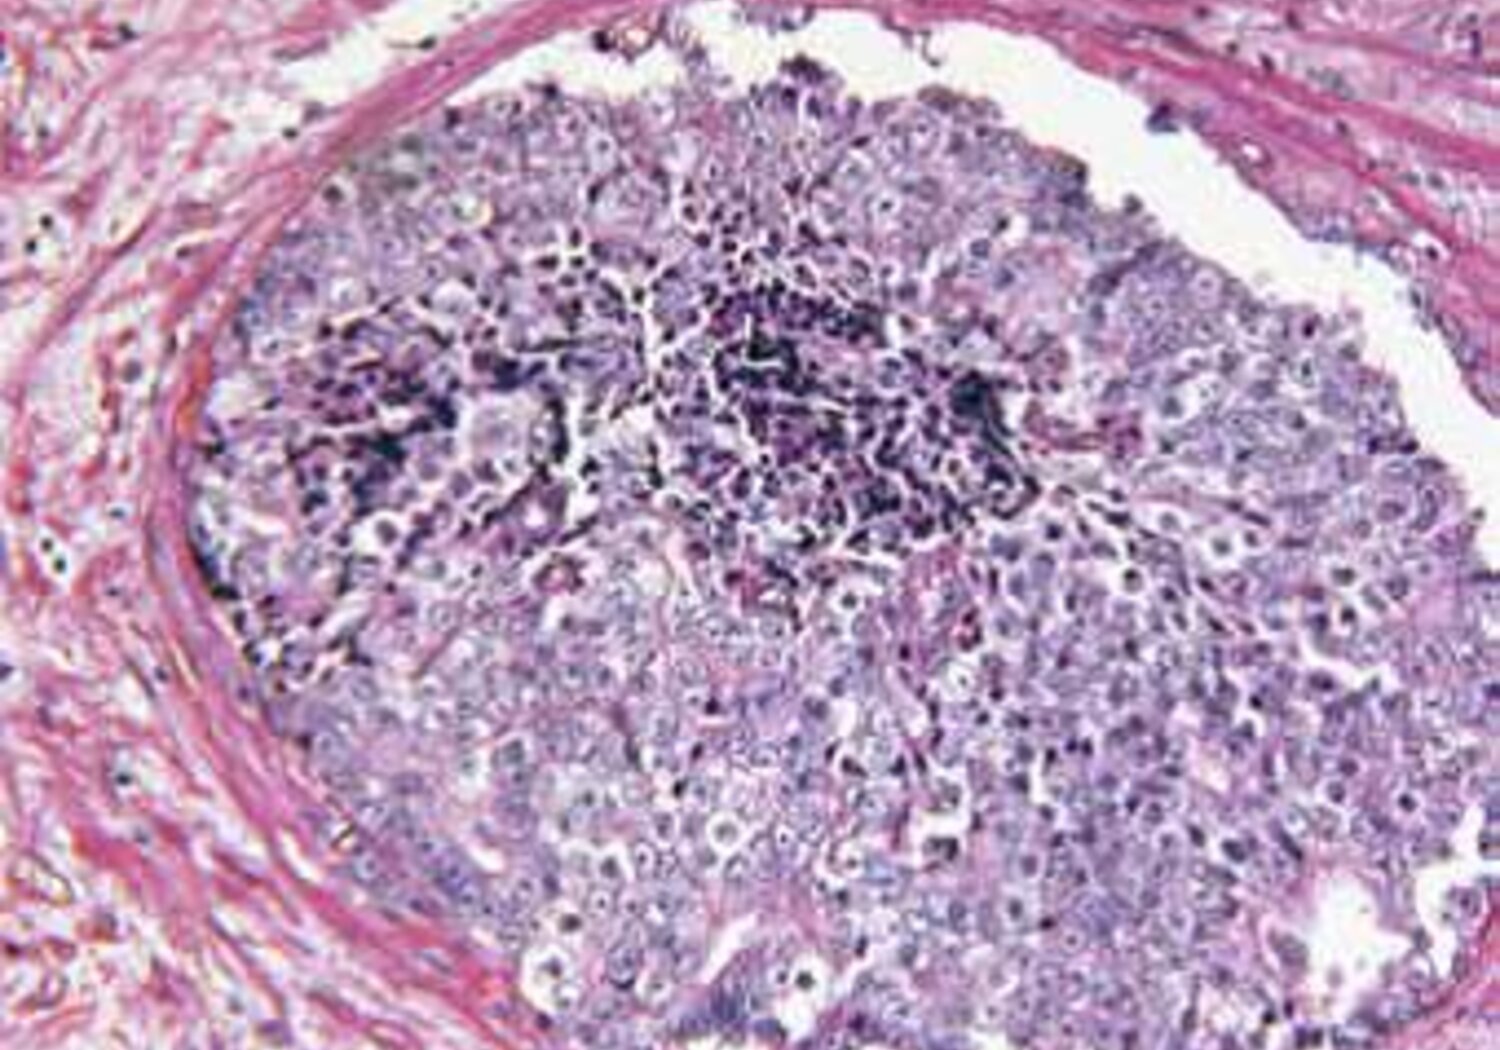

Molecular radiotherapy (MRT) specifically targets cancerous cells through the use of radioactive treatments that attach themselves to tumours in specific parts of the body, such as the liver. Currently, molecular radiotherapy is used in palliative care but it has the potential to become a first line treatment for cancer. Tailoring MRT for individual patients relies on accurately measuring the radioactivity of the drug and determining the therapeutic dose delivered to the tumour.

The EMRP project HLT11 Metrology for molecular radiotherapy successfully divided the radiation treatment process into a series of steps that could be related to primary standards, and developed methods for verifying the accuracy of each step. The project investigated the use of imaging techniques, to determine the dose delivered to the target tumour site.